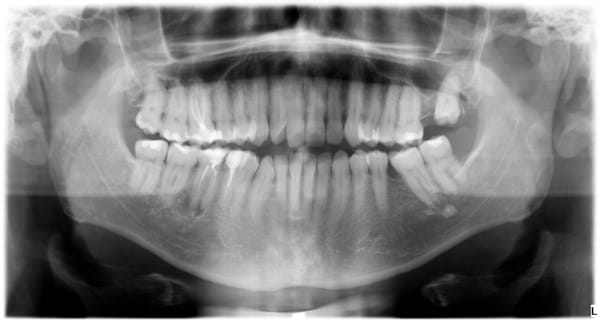

Hace 4 años me hicieron una endodoncia en Méjico no muy bien hecha, desde las primeras semanas me dolía un poco, la reconstrucción fue hecha en España pero al cabo de dos años empezó a fallar. Ahora me han hecho unas radiografías y me dicen que se una infección. Me comentan que la reendodoncia es complicada porque hay que quitar la que está hecha, esperar a que se desinfecte, volver a hacer la endodoncia y reconstrucción muy complicada debido a que la caries empezó muy abajo y pone una funda. Y es posible que aun así falle, así que me recomiendan un implante. Pongo las imágenes (es un molar abajo a la izquierda).

Respuesta